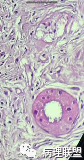

45岁 女性 左侧腮腺肿块

补充病史:4个月前发现左耳后肿块花生大小,无疼痛,最近一个月肿块不断增大,且触及有疼痛感。

补充大体描述:组织一块,大小4*3*2cm,切面见一肿块,大小2.6*2*1.8cm,肿块灰白灰黄,质偏硬,与周分界清楚。(病例由临床病理基础沙龙 程琼琳提供,致谢!)

补充昨天病例的图 像乳腺纤维囊性乳腺病的改变。

@程琼琳 您的病例标记肌上皮了吗?胶原化,小叶结构,大汗腺化生,,导管扩张,腺泡细胞泡沫变,嗜酸性变,除外下导管癌,挺像硬化性多囊性腺病的,最后您诊断什么?